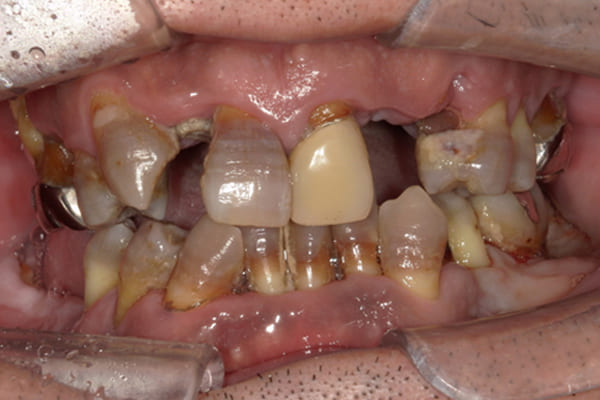

上前歯はブリッジの差し歯により根が折れ炎症を起こしお痛みのある状態でした。

原因は長期使用により下の義歯の歯が削れたことにより、下前歯が上前歯を突き上げ強い力が加わっていたことが根本的な原因と考えられます。

治療前は、奥歯が下がり、かみ合わせが乱れています。適切な入れ歯はそのままのかみ合わせで義歯を作るのではなく治療後のように、前歯から奥歯までのラインが真っすぐ揃った、かみ合わせの面を適切に付与し、よく咬め、残りの歯に負担がかからないかみ合わせとしました。

とにかく何も食べられないこと、人に会えないことから、なるべく早く何とかしたいとのご希望でした。

患者様とご相談の上、まず早急に上記を回復させるため、初診含め3度の来院でお食事ができ、見た目を回復できるように治療用義歯を作製、装着しました。

本来は、数本の上前歯の折れてしまって残せない歯は抜いてから歯肉の治癒を待ち、数か月後に型どりから作製になりますが、抜歯即時義歯といって、歯を抜く前に型、かみ合わせをとり、抜歯を行ったその日に上下の義歯を装着する特殊な治療法を用いたことで、10日後には治療用義歯をお口に装着することができ、お痛みもなくお食事ができ、ご友人とのお食事にも行けることが可能になりました。

本来、入れ歯作製は技工所と言って、義歯を作製する所に発送するため、作製には時間がかかりますが、院内に技工専用スペースを完備しており、長年、義歯治療において、技工も技術の習得してきましたので技工士さんではなく、かみ合わせの道具も私自身で院内で作製したことで、初診日の次の日にご来院いただきかみ合わせを採ることで、診断、型どり、かみ合わせ、装着まで10日という最短のご希望にこたえらた方です。

根のみの7本は虫歯にもなっており歯肉は腫れあがっています。

残りの歯もレントゲンで重度の歯周炎によりぐらぐらな状態でした。

治療前の入れ歯の奥歯は、治療後の義歯と比較しても分かるように、歯が削れ平らになった状態です。

これにより奥歯のかみ合わせは低くなり、前歯のみが強くあたり、かみ合わせにより上の前歯大きな負担がかかっていたことにより、上の前歯が折れたことが考えられます。